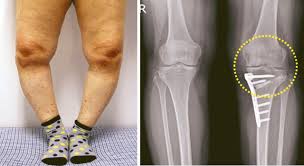

정상적인 다리 정렬에서는 체중이 무릎 중앙에 균등하게 분포되며, 관절에 가해지는 압력이 일정하다. 하지만 비정상적인 정렬, 즉 O자형(내반슬)이나 X자형(외반슬) 다리는 무릎 관절의 특정 부위에 과도한 압력을 가하게 된다. 이러한 압력 불균형이 장기간 지속되면 관절 연골이 점진적으로 마모되면서 관절염이 발생할 가능성이 높아진다.

O자형 다리(내반슬)는 무릎 관절의 내측(안쪽)에 더 많은 부담을 주는 형태로, 이로 인해 내측 연골이 빠르게 닳고 관절염이 심화될 가능성이 크다. 연구에 따르면 O자형 다리를 가진 사람은 정상적인 정렬을 가진 사람보다 무릎 관절염 발병률이 높으며, 관절염이 진행됨에 따라 다리의 변형이 더욱 심해지는 경향을 보인다. 이는 관절염으로 인한 연골 손실이 무릎의 특정 부위에서 더욱 집중적으로 발생하기 때문이다.

X자형 다리(외반슬)는 반대로 무릎 관절의 외측(바깥쪽)에 더 큰 부담을 주는 형태이다. X자형 다리는 비교적 드물지만, 특정 원인(예: 류마티스 관절염, 선천적 변형 등)으로 인해 발생할 수 있다. X자형 다리를 가진 경우, 무릎의 외측 연골이 급격하게 닳게 되어 관절염이 유발될 가능성이 있다.